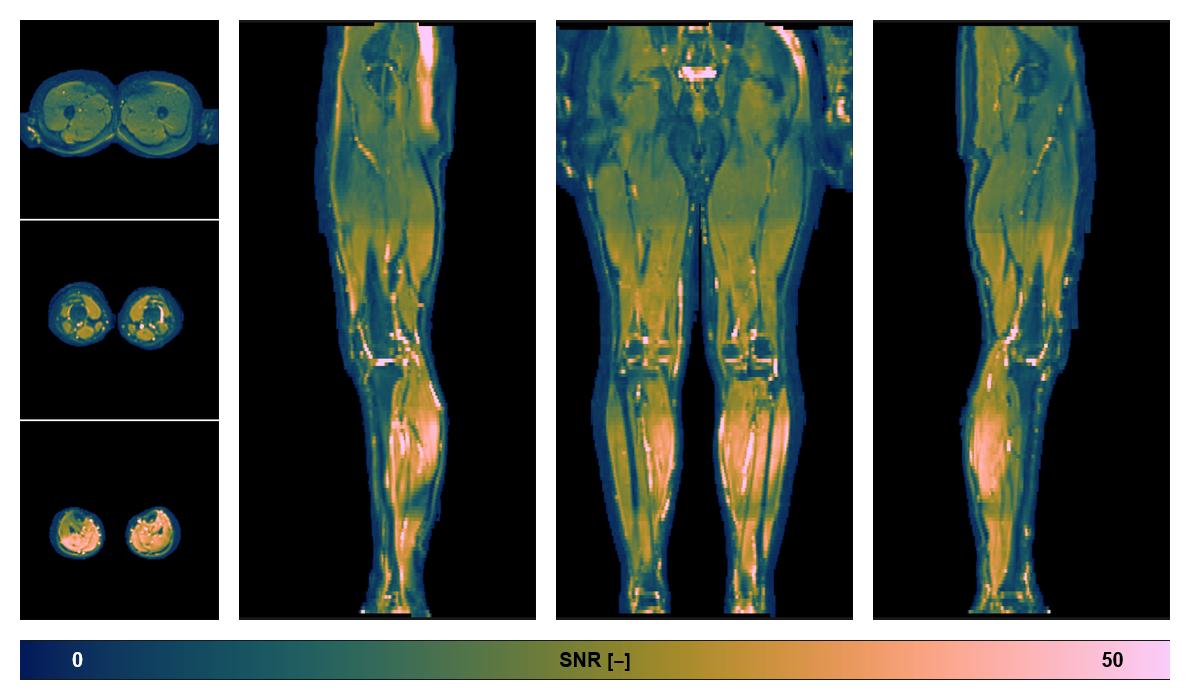

• SNR of the unweighted image

SNR distribution of the unweighted diffusion data.